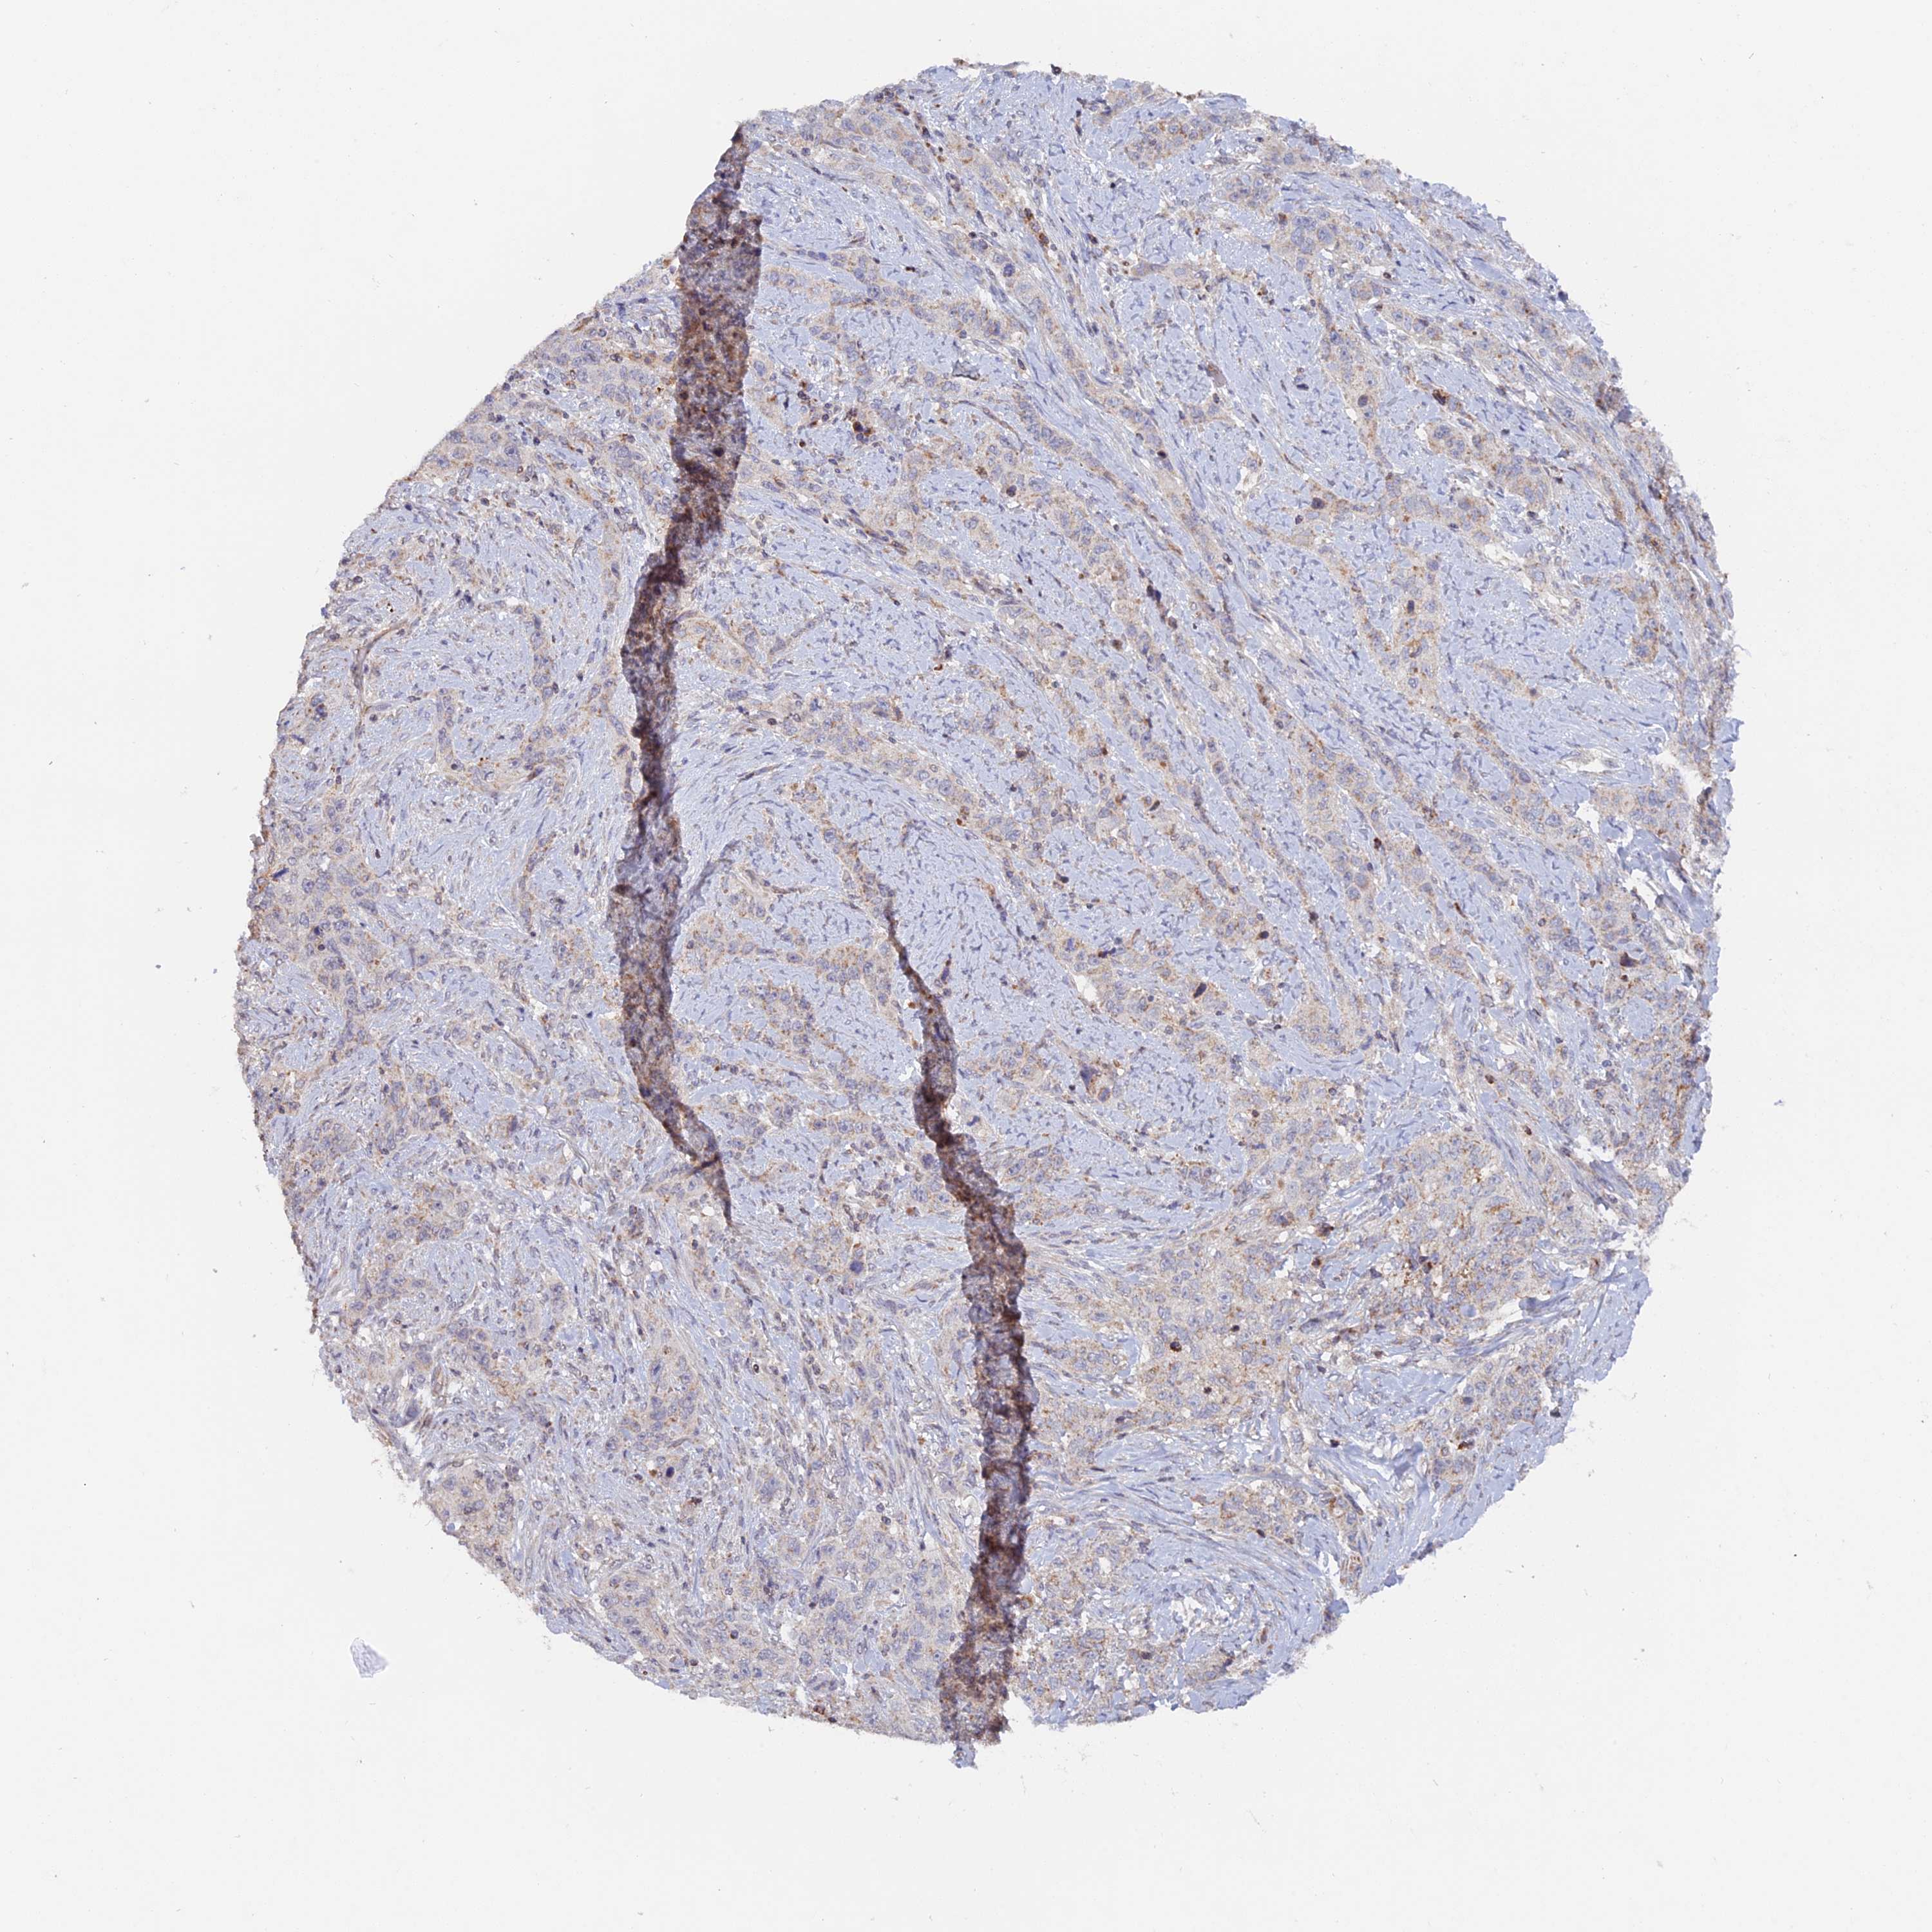

STOMACH CANCER - Protein expressioni

A mouse-over function shows sample information and annotation data. Click on an image to view it in a full screen mode. Samples can be filtered based on level of antibody staining by selecting one or several of the following categories: high, medium, low and not detected. The assay and annotation is described here.

Antibody stainingi

Antibody staining in the annotated cell types in the current human tissue is reported as not detected, low, medium, or high, based on conventional immunohistochemistry profiling in selected tissues. This score is based on the combination of the staining intensity and fraction of stained cells.

Each image is clickable and will lead to virtual microscopy that enables deeper exploration of all samples and also displays staining intensity scores, fraction scores and subcellular localization as well as patient and tissue information for each sample.

Antibody HPA041180

Staining

High

Medium

Low

Not detected

Intensity

Strong

Moderate

Weak

Negative

Quantity

>75%

75%-25%

<25%

None

Location

Nuclear

Cytoplasmic/membranous

Cytoplasmic/membranous,nuclear

Adenocarcinoma, NOS